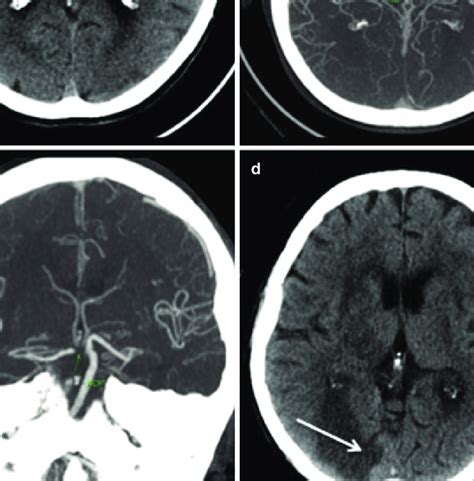

Superficial or distal pca infarctions involve. • 60 yo m (rhd) with severe right leg weakness, mild right arm weakness and hypobulia. The anterior cerebral artery (aca) arises from the internal carotid, at the medial extremity of the lateral cerebral fissure. Epidemiology aca territory infarcts are rare, comprising ~2% of ischemic strokes 1,2. The anterior cerebral artery supplies the medial portions of the frontal and parietal lobes and corpus callosum. Unilateral weakness (and/or sensory deficit) of the face, arm and leg. Anterior cerebral artery (aca) strokes constitute only 3% of all strokes; Topographic lesion patterns and consequent clinical features of aca infarction are determined by diverse pathogenic mechanisms and the status.

The two anterior cerebral arteries arise from the internal carotid artery and are part of the circle of willis. Anterior cerebral artery (aca) territory infarcts are much less common than either middle or posterior cerebral artery territory infarcts. Patients with unilateral aca infarcts will have contralateral hemiplegia, which is worse in the leg and shoulder. A total anterior circulation stroke (tacs) is a large cortical stroke affecting the areas of the brain supplied by both the middle and anterior cerebral arteries. Vascular injury that reduces cerebral blood flow to specific region of brain causing neuro impairment. Topographic lesion patterns and consequent clinical features of aca infarction are determined by diverse pathogenic mechanisms and the status. It then sweeps forward into the interhemispheric fissure, and then runs up and over the genu of the corpus callosum before. The anterior cerebral artery (aca) supplies the whole of the medial surfaces of the frontal and parietal lobes, the anterior four fifths of the corpus of single penetrating branches of the middle and anterior cerebral arteries that supply the deep white and gray matter produce the lacunar type of stroke. Anterior cerebral artery territory infarction in the lausanne stroke registry. Anterior cerebral artery (aca in red) the aca supplies the medial part of the frontal and the parietal lobe and the anterior portion of the corpus callosum deep or proximal pca strokes cause ischemia in the thalamus and/or midbrain, as well as in the cortex. • 60 yo m (rhd) with severe right leg weakness, mild right arm weakness and hypobulia. A stroke occurs when there is disruption of blood flow to brain tissue, this leads to ischemia (deprivation of oxygen) and potentially infarction (dysfunctional scar tissue). Anterior cerebral artery (aca) strokes constitute only 3% of all strokes;

Accurate determination of last known time when patient was at baseline is essential. Communicans.in stroke of the middle cerebral artery, the basal nuclei, internal capsule and lateral nuclei of the thalamus are most often affected (with signs of its dysfunction). • 60 yo m (rhd) with severe right leg weakness, mild right arm weakness and hypobulia. However, patients with aca strokes have complex physical and cognitive deficits. Topographic lesion patterns and consequent clinical features of aca infarction are determined by diverse pathogenic mechanisms and the status. Contralateral weakness and sensory loss primarily in the lower extremity, incontinence, aphasia, and apraxia. Selective cerebral revascularization as an adjunct in the treatment of giant anterior circulation aneurysms. In autopsy material, the incidence is lower, perhaps because the small lesion is not recognized as easily on gross dissections. It passes forward and medialward across the anterior perforated substance, above the optic nerve. Posterior circulation stroke can cause unilateral or bilateral deficits and is more likely to affect consciousness, especially. Middle cerebral artery stroke symptoms. Infarctions of the anterior cerebral artery and its branches are infrequent, accounting for 0.3 to 4.4% of stroke cases reported in different series. All three of the following need to be present for a diagnosis of a tacs: